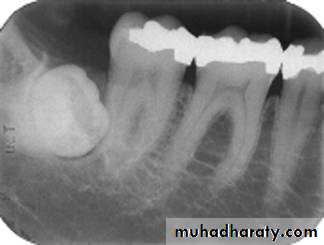

Bite-wing Radiography

• Indications:• Interproximal caries.

• Over-hang filling.

• Level of crestal bone between the teeth.

• Interproximal calculus.

• Principles:

• The film is placed in the mouth parallel to the crown of both upper & lower teeth.

• The film stabilized when the patient bites on the bite-wing tab or bite-wing film holder.

• The central ray of the x-ray beam is directed through the contacts of the teeth, using a +10 degree vertical angulation.

+10o vertical angulation is used to compensate for the slight bend of the upper portion of the film and the tilt of the maxillary teeth.

The molar-bitewing. A, Film placement. B, Resultant radiograph.

A

B